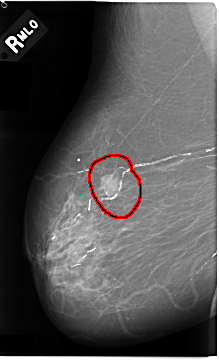

C_0031_1.RIGHT_MLO

FILE: C_0031_1.RIGHT_MLO.OVERLAY

TOTAL_ABNORMALITIES 1

ABNORMALITY 1

LESION_TYPE MASS SHAPE IRREGULAR MARGINS MICROLOBULATED

ASSESSMENT 5

SUBTLETY 5

PATHOLOGY MALIGNANT

TOTAL_OUTLINES 1

BOUNDARY